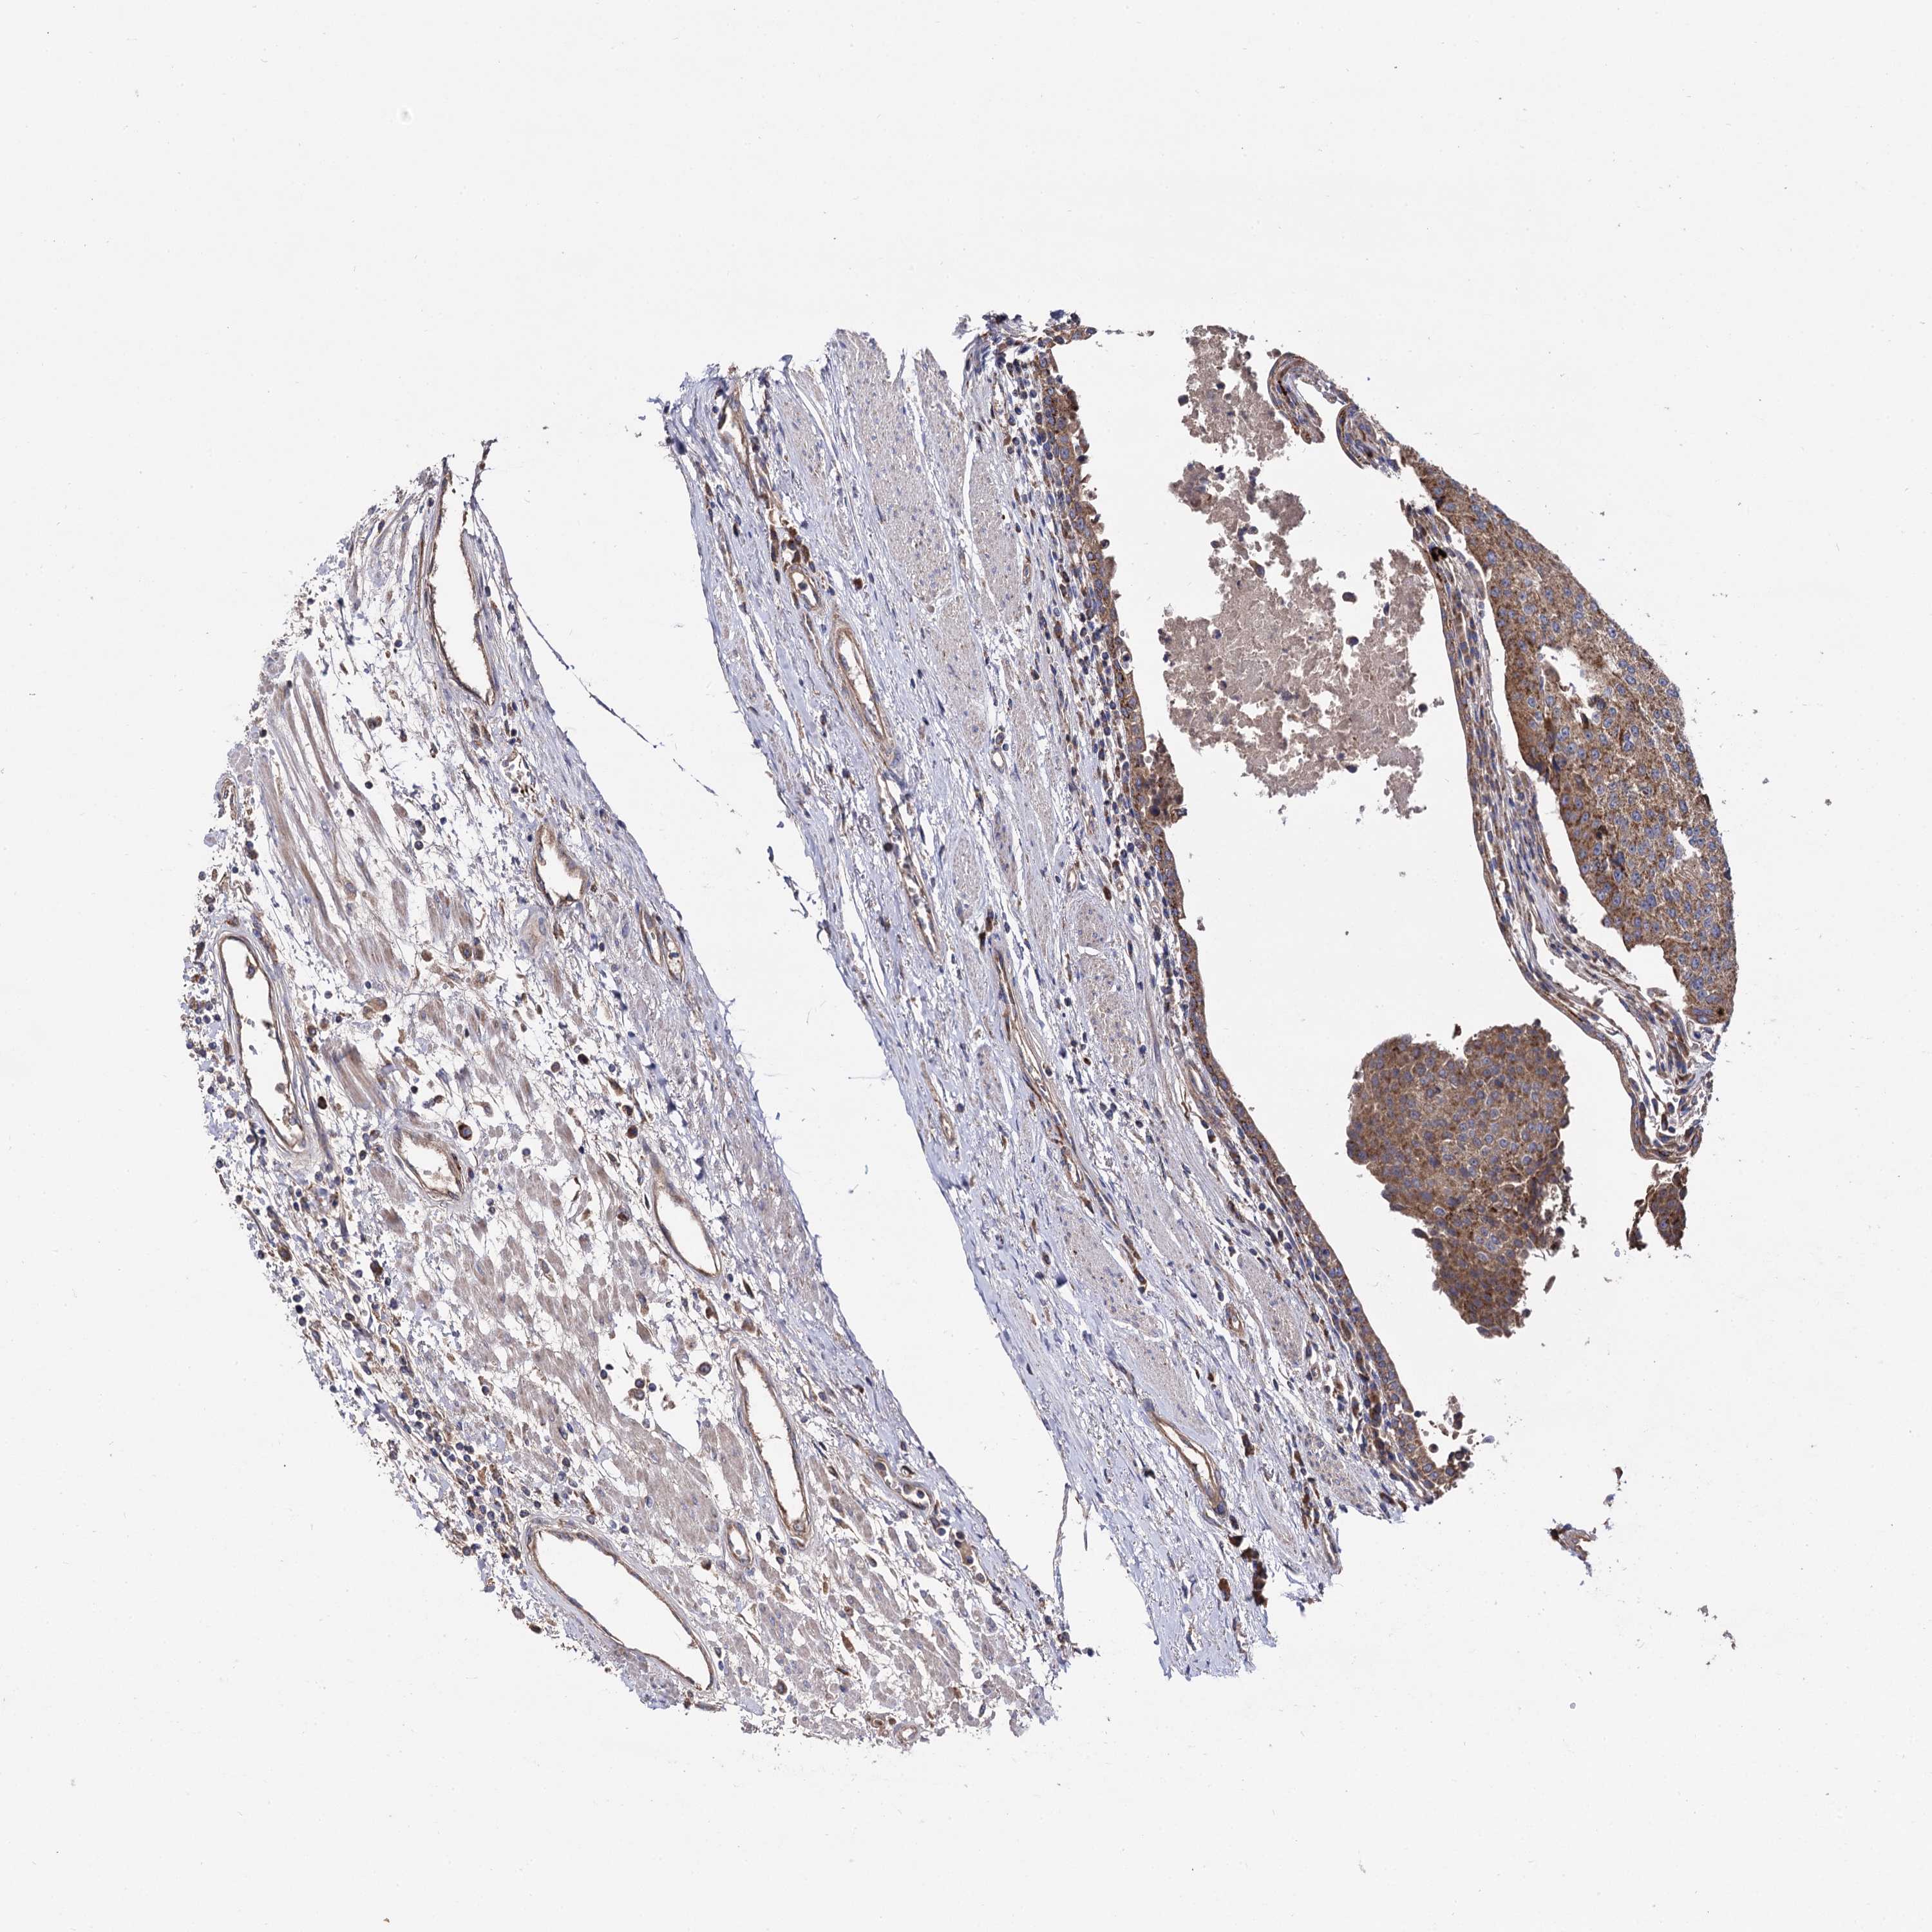

UROTHELIAL CANCER - Protein expressioni

A mouse-over function shows sample information and annotation data. Click on an image to view it in a full screen mode. Samples can be filtered based on level of antibody staining by selecting one or several of the following categories: high, medium, low and not detected. The assay and annotation is described here.

Note that samples used for immunohistochemistry by the Human Protein Atlas do not correspond to samples in the TCGA dataset.

Antibody stainingi

Antibody staining in the annotated cell types in the current human tissue is reported as not detected, low, medium, or high, based on conventional immunohistochemistry profiling in selected tissues. This score is based on the combination of the staining intensity and fraction of stained cells.

Each image is clickable and will lead to virtual microscopy that enables deeper exploration of all samples and also displays staining intensity scores, fraction scores and subcellular localization as well as patient and tissue information for each sample.

Antibody HPA040845

Staining

High

Medium

Low

Not detected

Intensity

Strong

Moderate

Weak

Negative

Quantity

>75%

75%-25%

<25%

None

Location

Nuclear

Cytoplasmic/membranous

Cytoplasmic/membranous,nuclear

Urothelial carcinoma, NOS